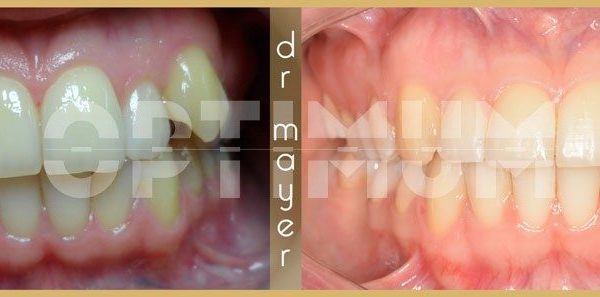

Az elmúlt évekből rengeteg szakmai referenciát tudnánk bemutatni, amelyek különböző fogszabályozási problémákat oldottak meg. Válogatva a több száz esetből, ezen az oldalon olyan képeket, információkat igyekeztünk bemutatni, amelyeknek a segítségével a jövőbeni pácienseinknek azt tudjuk üzenni: A Te fogsorod is lehet gyönyörű!

(Képeket a Pácienseink külön írásos beleegyezésével mutatjuk be!)